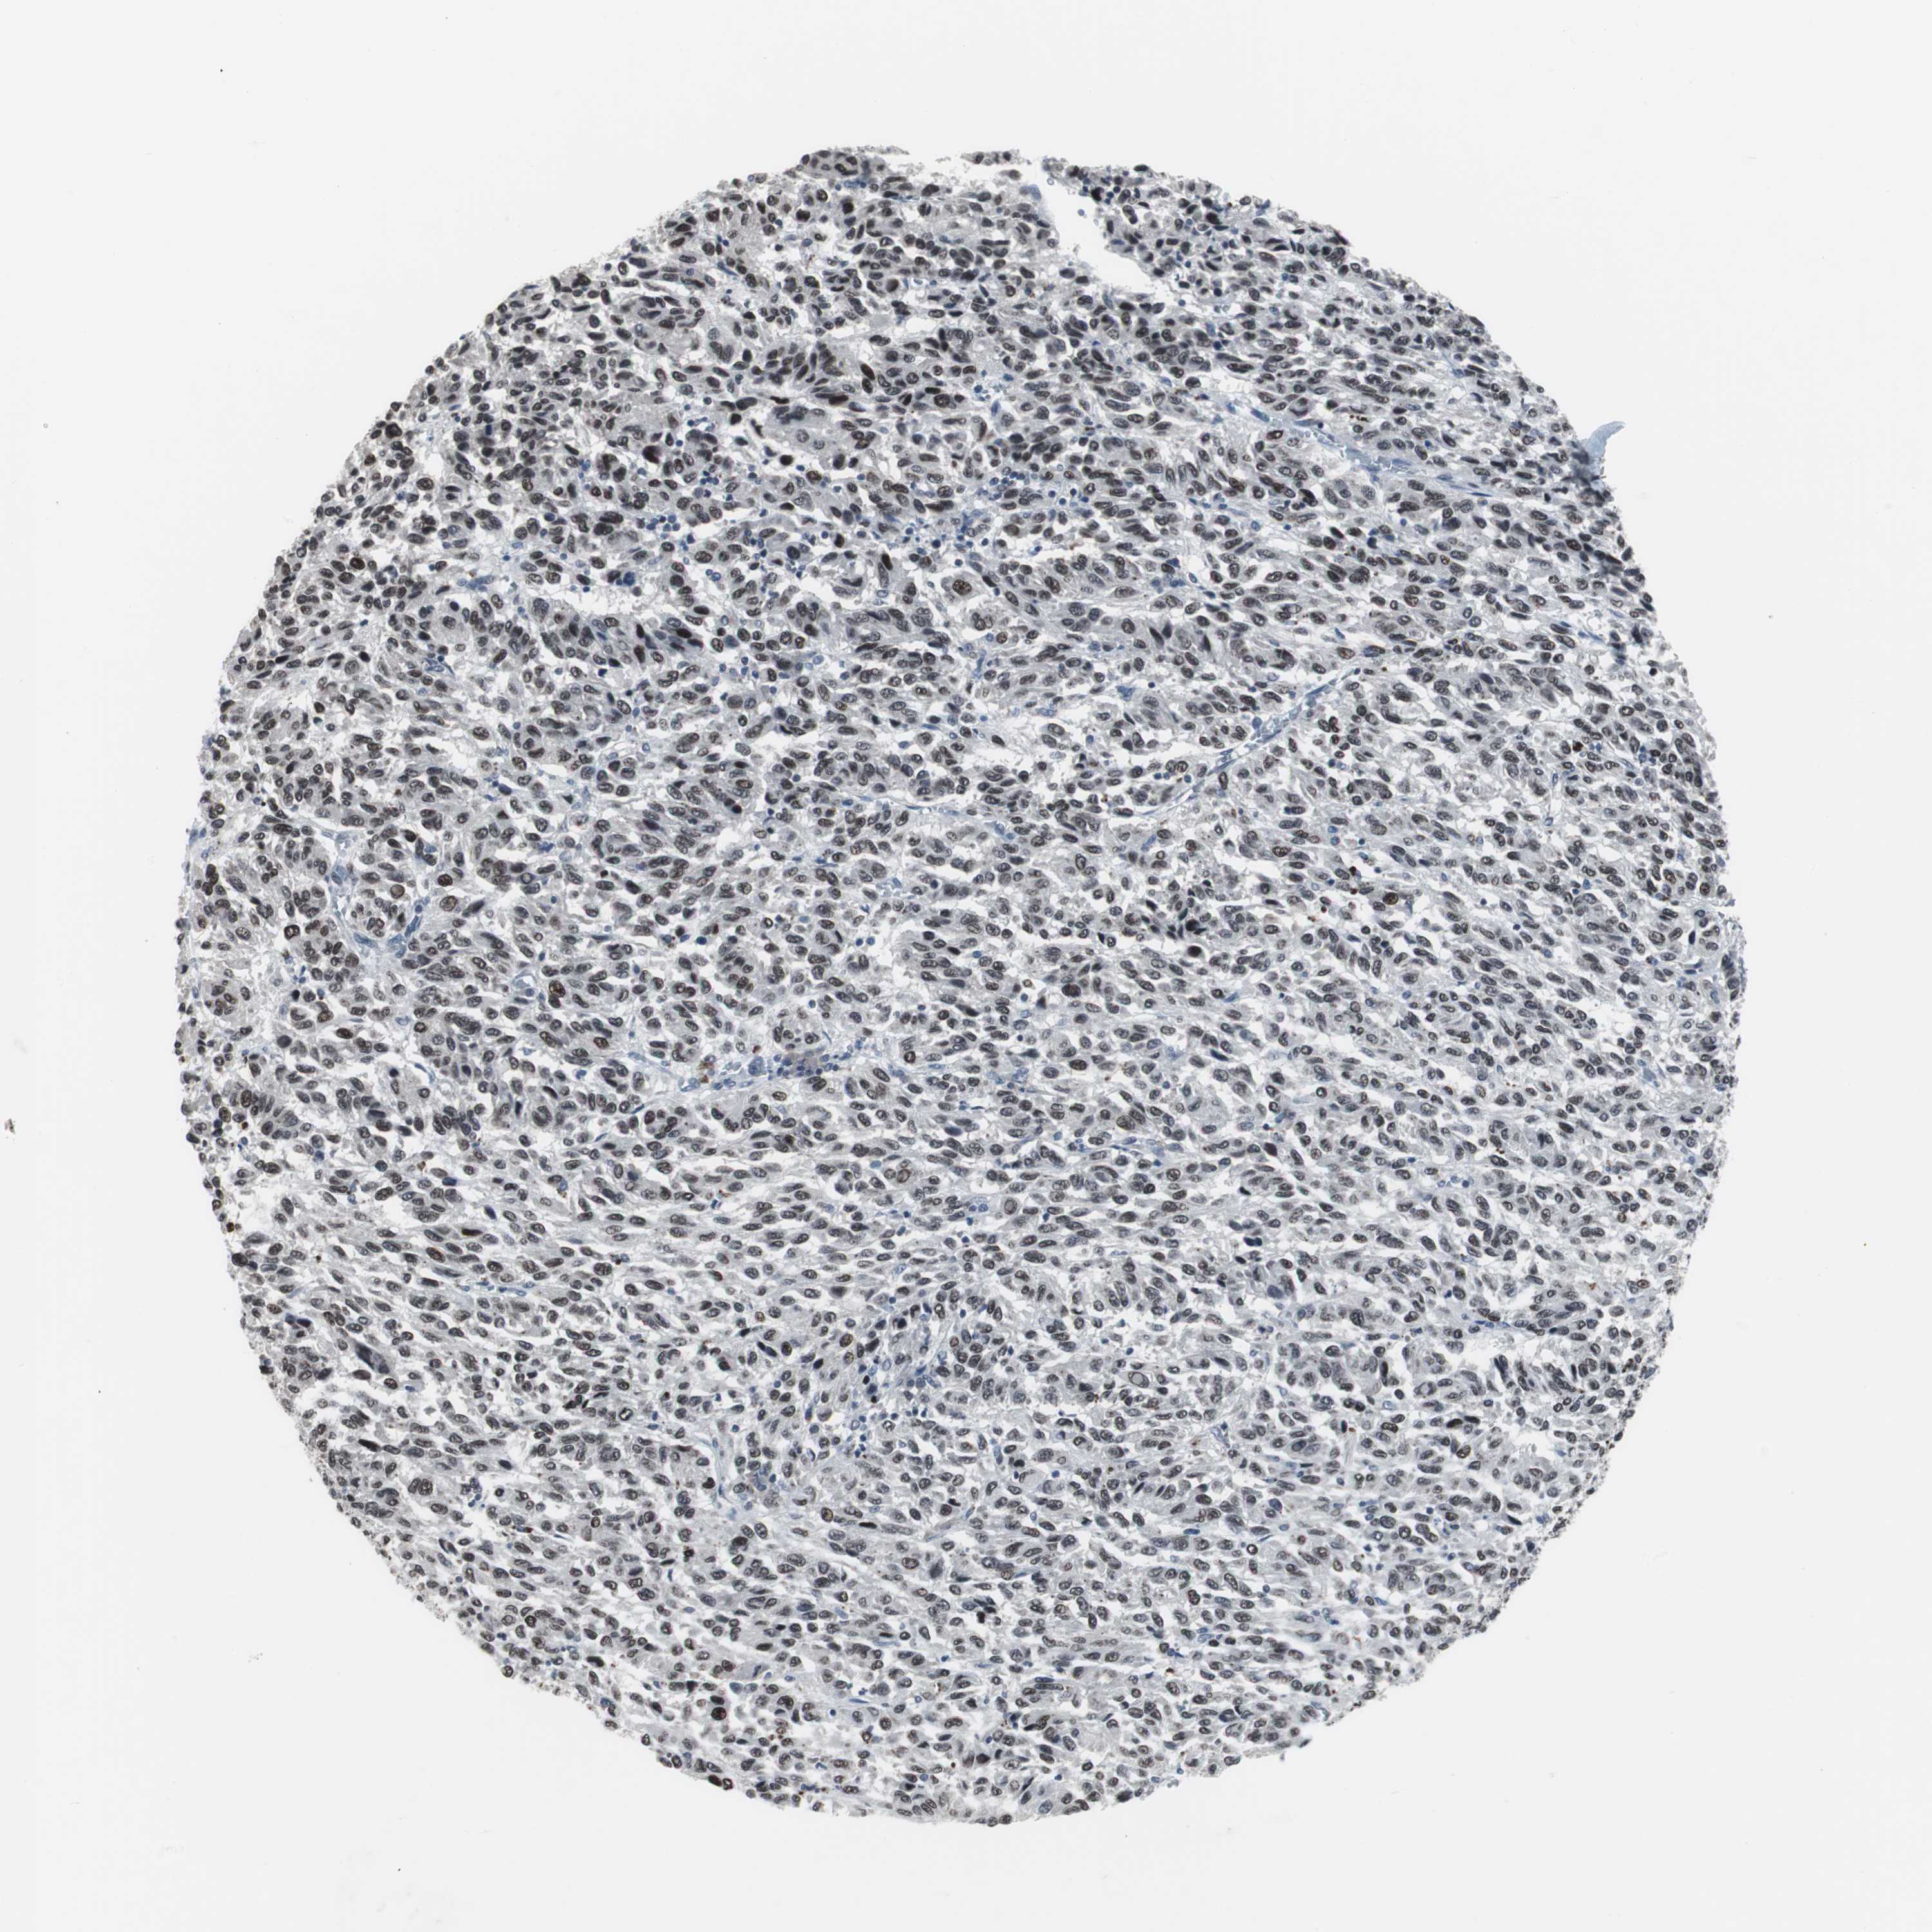

MELANOMA - Protein expressioni

A mouse-over function shows sample information and annotation data. Click on an image to view it in a full screen mode. Samples can be filtered based on level of antibody staining by selecting one or several of the following categories: high, medium, low and not detected. The assay and annotation is described here.

Note that samples used for immunohistochemistry by the Human Protein Atlas do not correspond to samples in the TCGA dataset.

Antibody stainingi

Antibody staining in the annotated cell types in the current human tissue is reported as not detected, low, medium, or high, based on conventional immunohistochemistry profiling in selected tissues. This score is based on the combination of the staining intensity and fraction of stained cells.

Each image is clickable and will lead to virtual microscopy that enables deeper exploration of all samples and also displays staining intensity scores, fraction scores and subcellular localization as well as patient and tissue information for each sample.

Antibody HPA007176

Staining

High

Medium

Low

Not detected

Intensity

Strong

Moderate

Weak

Negative

Quantity

>75%

75%-25%

<25%

None

Location

Nuclear

Cytoplasmic/membranous

Cytoplasmic/membranous,nuclear

Malignant melanoma, NOS

Malignant melanoma, Metastatic site